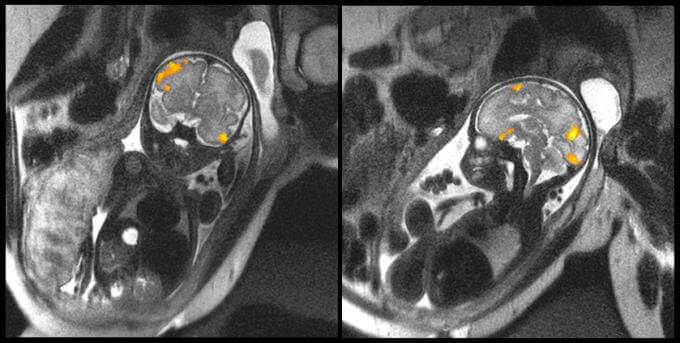

Nell’immagine superiore possiamo vedere la risonanza magnetica di un feto di 20 settimane e di un altro di 40. Sono immagini concesse dalla Facoltà di Medicina dell’Università Statale di Wayne (Michigan, Stati Uniti) che ci illustrano chiaramente l’attività cerebrale di due feti nell’utero materno.

Uno degli obbiettivi prioritari degli studiosi che hanno realizzato queste prove era quello di analizzare in che modo si connettono i neuroni durante le ultime settimane di gestazione. I dati ottenuti ci hanno rivelato aspetti fino a questo momento sconosciuti riguardo i bambini prematuri.